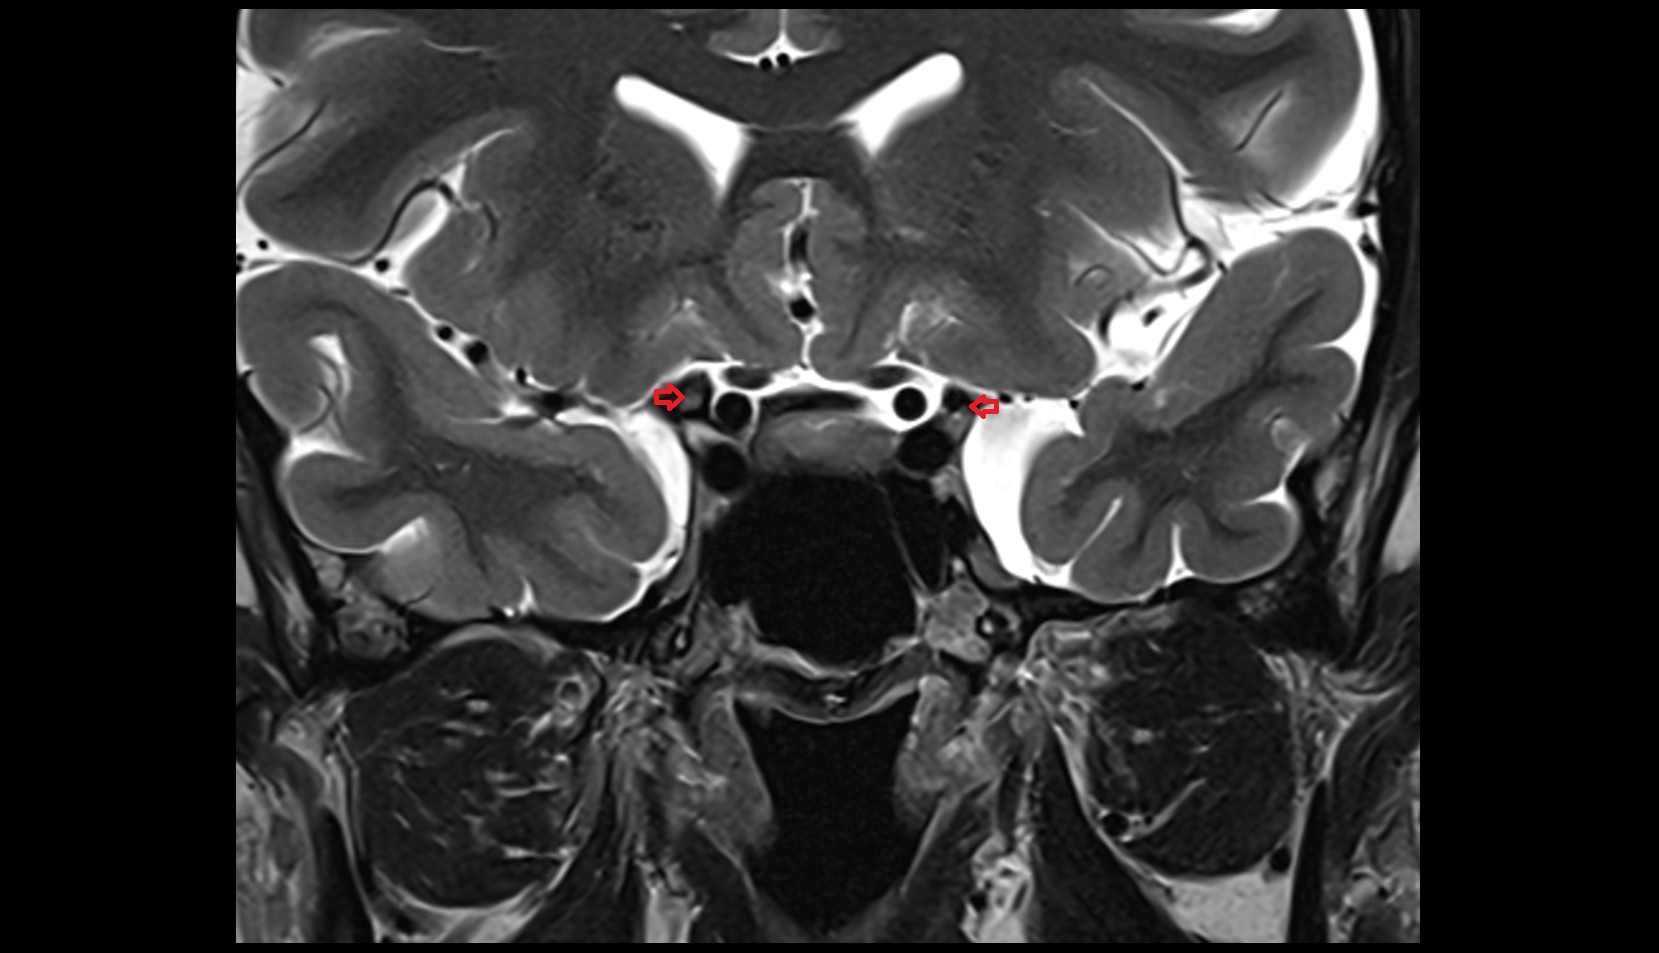

- Mandibular condyle

- Mandibular fossa

- Articular disc of temporomandibular joint

- Articular eminence

- Articular surface of mandibular fossa

- Intermediate zone of articular disc

- Temporomandibular joint